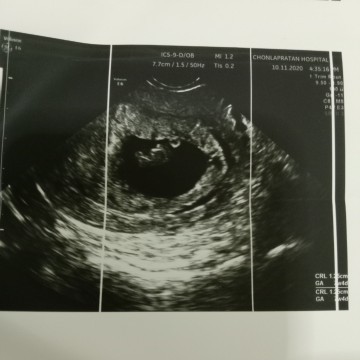

เห็นน้องกับหัวใจเต้นแล้วค่ะ บ้านนี้9 มิ.ย จ้า

1 มิ.ย. คะ เห็นหัวใจดวงน้อยๆของน้องแล้วคะ

25มิถุนายน64ค่ะ ซาวด์ตอน7w4d ตอนนี้11w4dแล้วค่ะ